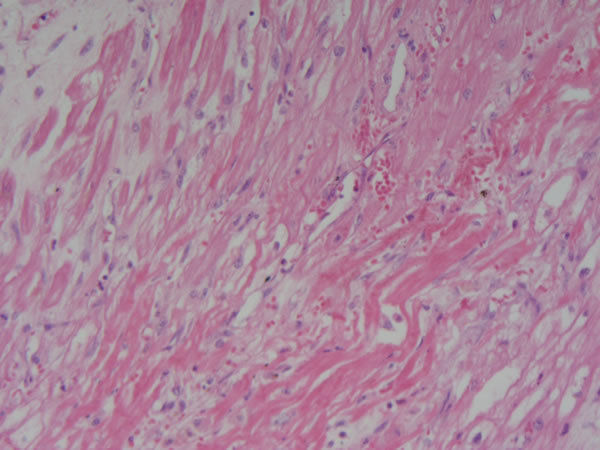

Icinesp2 (image/jpeg)

Pele - tec. pavimentoso estratificado, conj, e de granulação Reparo - fístula cutânea Outros achados: inflâmação crônica, inflamação aguda (apresenta área de solução de continuidade no centro) |

| Pele - tec. pavim. estratif., conj. e tecido de granulação Reparo - Fístula cutânea Causa: inf. bacteriana, Crohn | |

Image:

Pele - tec. pavim. estratif., conj. e tecido de granulação Reparo - Fístula cutânea Foco no tecido de granulação (novos vasos, muitas células de defesa) |

Pele - tec. pavim. estratif., conj. e tecido de granulação Reparo - Fístula cutânea Na parte de cima é o tecido já organizado/cicatrizado (mto fibroblasto) e na parte de baixo é tec. de granulação |